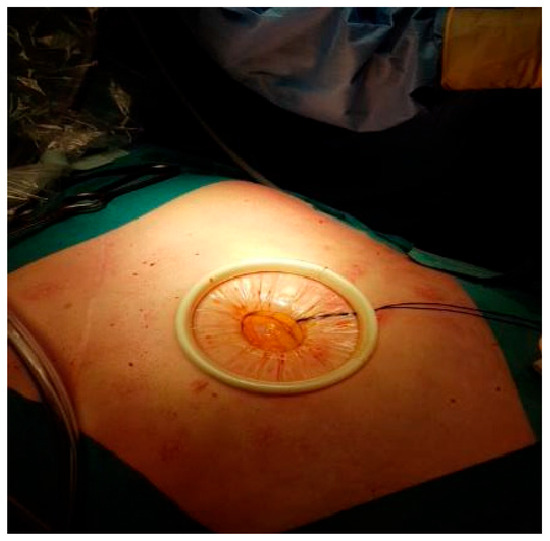

2.2. Operative Technique